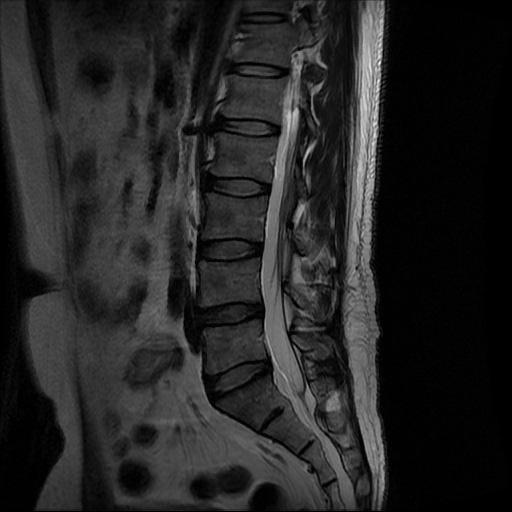

허리 MRI 디스크 상태 분석 부탁드립니다

검진 차 MRI찍었는데 분석 부탁드립니다.

건협에서는 관리해야 된다는데 디스크 협착이나 팽윤 등이 있는 상태인지 궁금합니다.

우선 현재로썬 사진만으론 판단을 하기에 제한이 되지만 사진상 디스크 상태는 심해보이지 않습니다.

요추부위의 하부 에서 약간의 팽윤이나 돌출로 의심해볼수 있는 정도이지만, 정확한 상태는 관련 전문의에게 진료시 문의를 하시는 것을 추천드립니다.